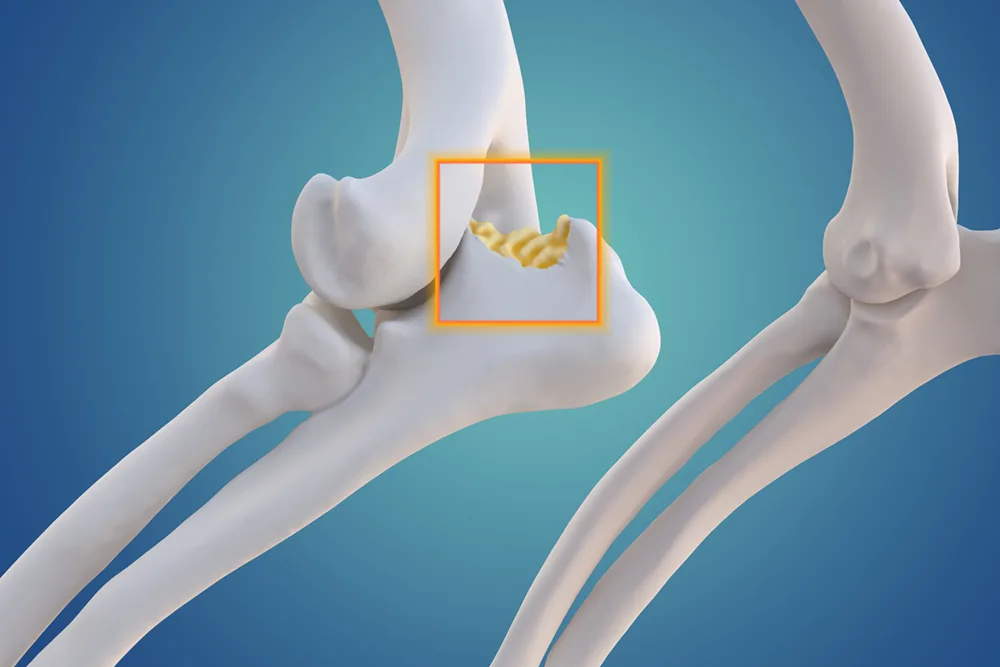

Osteoarthritis (OA) is one of the most common chronic conditions in dogs, and one of the most misunderstood. Many owners attribute stiffness, slowing down or irritability to ‘just getting old,’ when in reality these are signs of pain. Until recently, canine OA treatment options focused mainly on non-steroidal anti-inflammatory drugs (NSAIDs), joint supplements, weight management and physiotherapy.

But the release of Librella® (bedinvetmab) has introduced an entirely new class of pain relief: one that is long-acting, targeted, and specifically designed for chronic arthritis in dogs. If your dog has OA or is showing early signs, this medication may be part of the future of comfort-focused care.

Librella® works by targeting nerve growth factor (NGF), a key driver of osteoarthritis pain. When NGF attaches to its receptors, it increases the sensitivity of pain pathways. Librella® binds to NGF, blocking its activity and reducing pain signalling.

Stiffness after rest, especially when rising from sleep, is one of the earliest and most common signs of canine osteoarthritis, particularly in middle-aged and senior dogs.

SIGNS SUGGESTING ARTHRITIS

• Slow to stand after lying down

• Hesitation on stairs or jumping into cars

• ‘Bunny hopping’ or altered gait

• Less interest in long walks

• Stiffness that improves as they ‘warm up’

• Irritability when touched over hips, back or elbows

OTHER CONDITIONS THAR MIMIC ARTHRITIS

• Muscle strain

• Cruciate ligament disease

• Neurological weakness

• Hip or elbow dysplasia

• Lyme disease or immune-mediated joint disease

A vet exam and possibly X-rays are the best way to confirm.